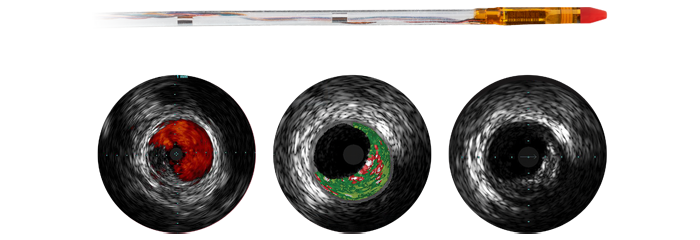

Для все большего числа пациентов с ИБС выбирается минимально инвазивное лечение, однако в этом случае оптимальному планированию лечения препятствует тот факт, что для коронарной ангиографии в режиме 2D существуют ограничения по обнаружению и оценке коронарного стеноза. Данные, получаемые до и во время процедуры, не объединяются согласованно и надлежащим образом, что увеличивает время лечения и усложняет его планирование. Разработанные нами решения для кардиологических исследований устраняют эти проблемы, чтобы вы могли реализовать преимущества клинической эффективности в своей рентгеноперационной:

Ангиография, iFR, ВСУЗИ и мониторинг гемодинамических параметров, а также предварительное планирование кардиологических интервенций и экспертные приложения интегрированы в единый интерфейс ангиографической системы, что обеспечивает просмотр, управление и настройку конфигурации на мониторе с помощью одного контроллера у стола или из пультовой.